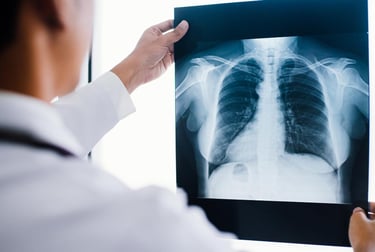

Radiografia (Raio-X)

Exame de imagem que utiliza radiação para visualizar estruturas internas do corpo, sendo amplamente utilizado na avaliação de pulmões, ossos e outras regiões.